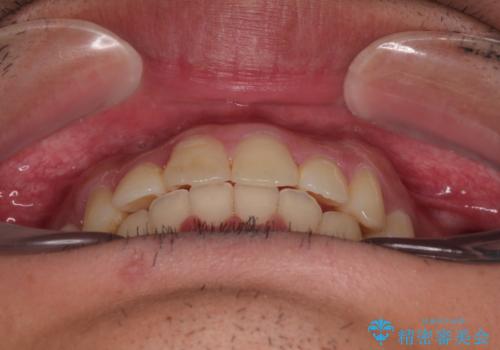

デコボコをインビザライン矯正で改善 奥歯は補助装置で確実に移動を

補助装置を併用せずに治療を終える可能性はありましたが、確実に結果を得るために補助装置を活用しました。

イメージしたとおりの仕上がりとなりました。